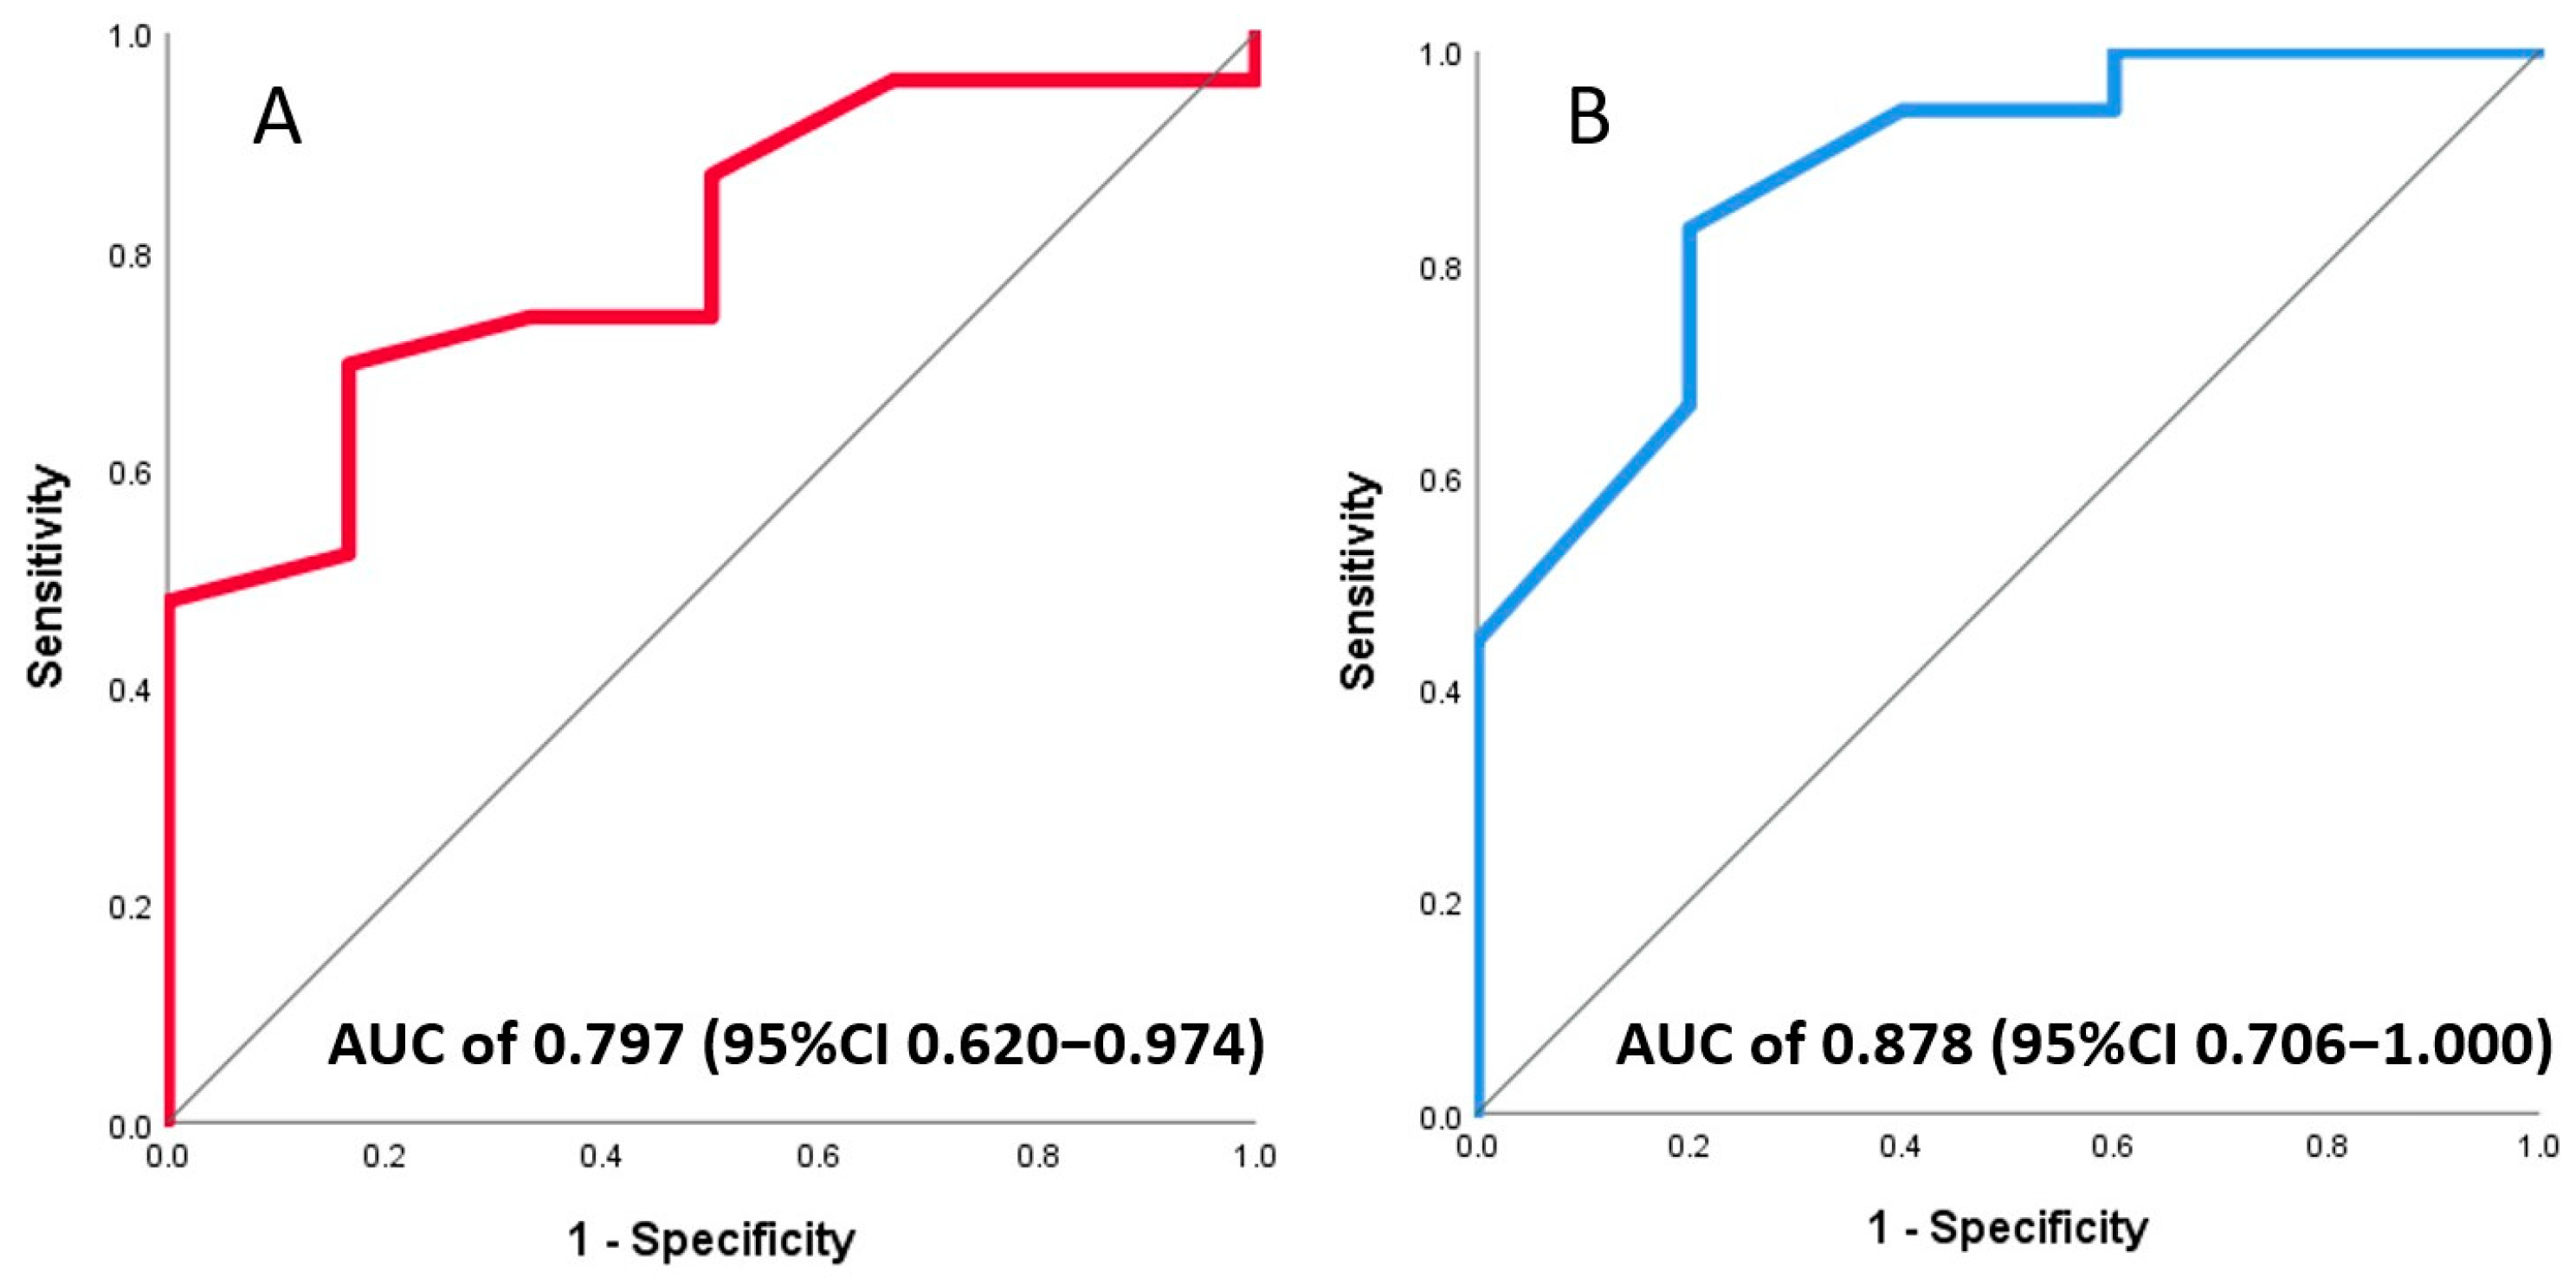

3.3. Association of Invasive and Non-Invasive CFR with Final Infarct Size

3.4. Association of Invasive and Non-Invasive CFR with LV Function

4.2. Echocardiography-Derived CFR Predicts Infarct Size and LV Function after STEMI